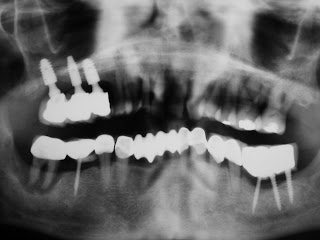

Granted that we need to use a titanium screw, since the tooth germ implant is not yet available….. it does make more organic living sense to use the optimal titanium necessary to allow maximal living tissue around it and thus also minimize the perio pocket that inevitably forms around all dental implants.

Minimized and optimized diameter implants should be the trend and not large diameter dental implants. If we have to put something foreign into the living body, put in the smallest you can. That is what the “GREEN MOVEMENT” is all about…… to use just enough and leave the rest alone and we will save the world !